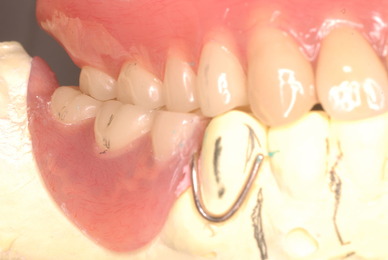

上の歯は一本がブラブラでしたね。

カビのような汚い部分を除去した直後です。